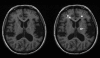

Background: The accuracy of texture analysis in clinical evaluation of magnetic resonance images depends considerably on imaging arrangements and various image quality parameters. In this paper, we study the effect of slice thickness on brain tissue texture analysis using a statistical approach and classification of T1-weighted images of clinically confirmed multiple sclerosis patients.

Methods: We averaged the intensities of three consecutive 1-mm slices to simulate 3-mm slices. Two hundred sixty-four texture parameters were calculated for both the original and the averaged slices. Wilcoxon's signed ranks test was used to find differences between the regions of interest representing white matter and multiple sclerosis plaques. Linear and nonlinear discriminant analyses were applied with several separate training and test sets to determine the actual classification accuracy.

Results: Only moderate differences in distributions of the texture parameter value for 1-mm and simulated 3-mm-thick slices were found. Our study also showed that white matter areas are well separable from multiple sclerosis plaques even if the slice thickness differs between training and test sets.

Conclusions: Three-millimeter-thick magnetic resonance image slices acquired with a 1.5 T clinical magnetic resonance scanner seem to be sufficient for texture analysis of multiple sclerosis plaques and white matter tissue.